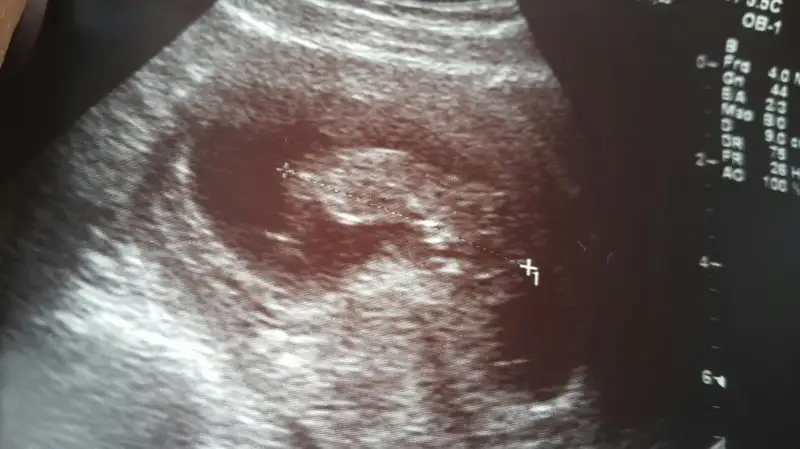

Kızlar üç günlük rapor yazdı düsuk tehditi var die. Yatış yapcakti istemedim. Bu da fotosu 11+0 . Aranızda cinsiyet tahmini yapabilecek var mı. Biliorum çok erken ama . Tahmin sonuçta söyleyin bişiler

Eklentiler

• 2015-11-17 12.53.54.webp

21 KB · Görüntüleme: 129